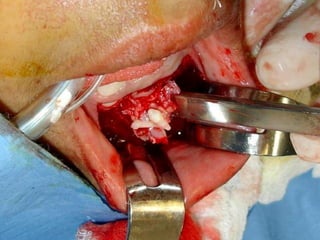

Eliminación de focos sépticos en bloque en paciente con osteitis

mandibular crónica

Imagen microscópica de osteitis, inicialmente existe una etapa de

osteoclastosis seguida por regeneración. No siempre el hueso

regenera en su totalidad y sigue el curso de cualquier inflamación

dejando un area de tejido fibroso que con el tiempo puede

calcificarse (hueso denso)

Manejo con antibióticos obligado

Revisión periódica